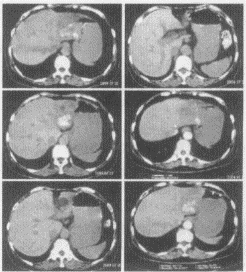

女,60歲,上腹痛10個月,近來加劇。疼痛以夜間為重,坐起可緩解,向背部放射,胃納差,近期體重下降。實驗室檢查正常。

3.患者所做檢查圖如下,你考慮為何種疾病?